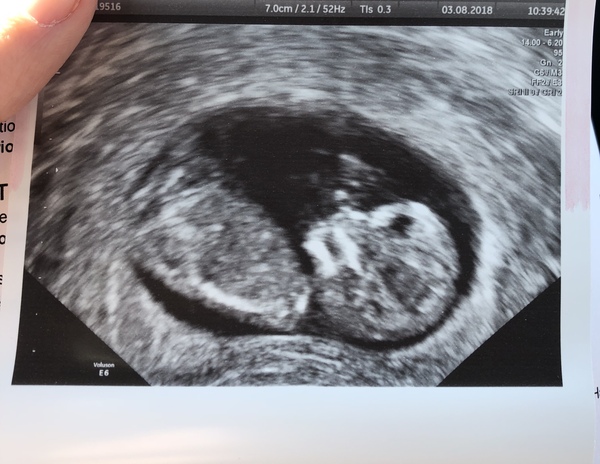

MakeLemonade · 03/08/2018 17:04

Had our nuchal scan today. Hey baby 👋🏻

Down’s risk was 1 in 10,000(ish) and the other two less than 1 in 20,000 so low risk.